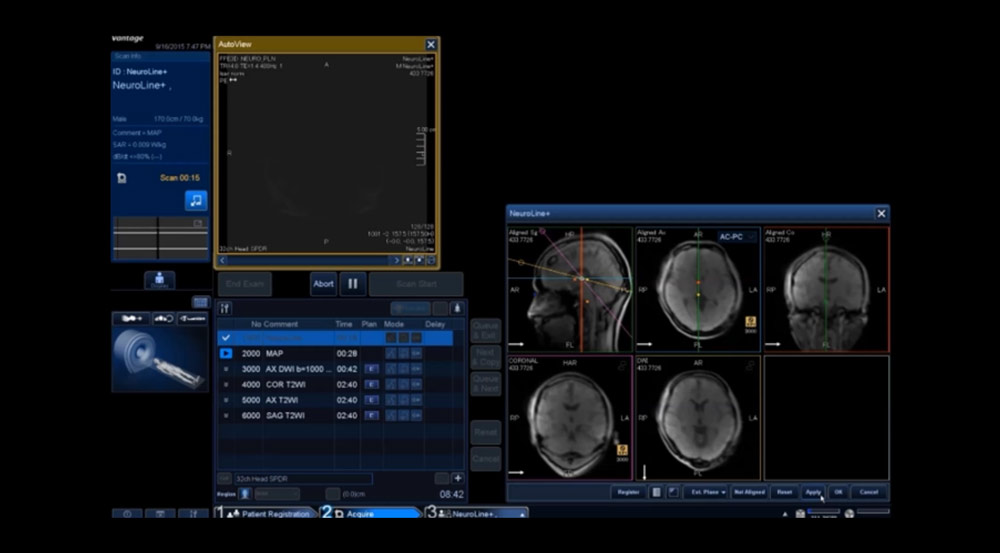

Программная платформа M-Power последнего поколения с интегрированными приложениями облегчает все этапы исследования, начиная с регистрации пациента и заканчивая пост-обработкой и анализом данных. Кроме того, различные приложения помогают правильно позиционировать пациента, например, при спинальных исследованиях или сканировании мозга.

Функционал EasyTech — это полностью автоматическое планирование исследований:

NeuroLine - автоматически планирует исследование головного мозга. Обеспечивает непревзойденную согласованность сканирования для всех ваших исследований мозга. Интеллектуальный алгоритм выравнивания функции позволяет автоматически настраиваться в соответствии с AC-PC и линией OM.